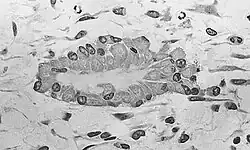

Při tzv. enchondrální osifikaci, která je typická pro většinu lidských kostí,[2] nejprve dochází ke vzniku (hyalinního) chrupavčitého modelu budoucí kosti z původní mezenchymální tkáně v lamelární kosti. V dalším kroku vzniká uprostřed tohoto chrupavčitého modelu (v oblasti známé jako diafýza) zárodek kostní tkáně – první kostní buňky (osteoblasty) vznikají z vnitřních buněk perichondriálního obalu chrupavky. Do chrupavky se dostávají vápenaté soli a celá chrupavka je následně naprosto zacementována do té míry, že jsou buňky chrupavky odříznuty od kyslíku a živin a umírají. Teprve poté si do tohoto „cementu“ razí cestu krevní vlásečnice, rozrušujíc mrtvou chrupavčitou tkáň. Tím vzniká pórovitá struktura, posléze známá jako kostní dřeň. V jádru kosti se ustanoví tzv. primární osifikační jádro; z něj se kostní osteoblasty (ale i osteoklasty s neméně důležitou rolí) šíří do všech částí budoucí kosti. Postupně se dostávají až do oblasti růstových plotének, tedy oblastí, kde neustále vzniká nová chrupavka, odstupuje do stran, mineralizuje a po osídlení kostními buňkami se mění v regulérní kost. Tím kost roste do délky. Zároveň se kostní buňky ukládají i pod okosticí, což umožňuje růst kosti do šířky.[1]

Kostnatěním vaziva

U člověka je tato tzv. intramembranózní osifikace vzácnější,[2] ale i tak poměrně významná. Princip je prostý: nevzniká žádná přechodná chrupavčitá tkáň – veškerá kostní tkáň se totiž tvoří přímo z mezenchymálních buněk v původní zárodečné lamelární kosti. Mezenchym se nejprve uspořádává do jistých vrstev (membrán) a z toho byl také odvozen název tohoto typu kostnatění. Mezenchymální buňky se shlukují a objevuje se mezi nimi gelovitá mezibuněčná hmota. Jak se objevují první osteoblasty a krevní zásobení, gelovitá hmota je nahrazována kompaktnějšími tyčinkami kostní hmoty a mineralizuje se. Kostní buňky na povrchu vznikající kosti se dělí a produkují další kostní hmotu – takovým způsobem kost přirůstá.[1]